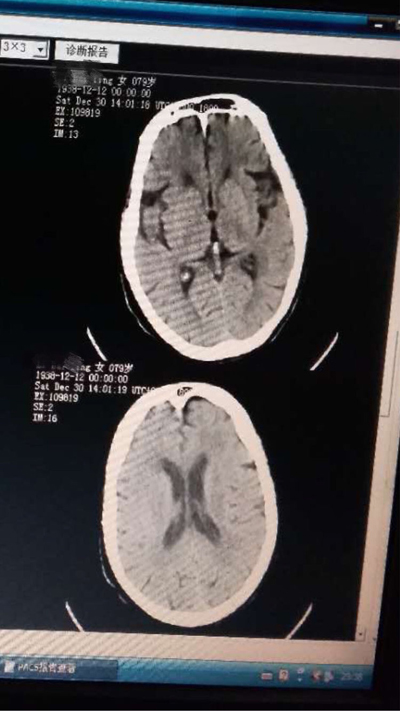

病例一:第一例脑梗死行尿激酶静脉溶栓治疗

患者黎某某,女,79岁,白水镇白水村人,因胸闷、气促半月入住内一科诊断为冠心病,心功能三级,于2017年12月12日13时突发口角歪斜,神志不清,考虑脑梗死可能性大。查体:浅昏迷,检查不配合,口角左斜,伸舌不能,四肢肌力检查不配合,肌张力正常,右侧巴氏征(+)。

溶栓前头部CT,排除脑出血

立即请神内会诊,神内非常重视该患者,迅速做完评估,头颅CT未见梗死及出血,患者无静脉溶栓禁忌症,跟家属谈话对溶栓风险表示理解,立即启动尿激酶静脉溶栓,患者于两个半小时后神志恢复,未留后遗症。

第二天复查头颅CT未见出血及梗死灶